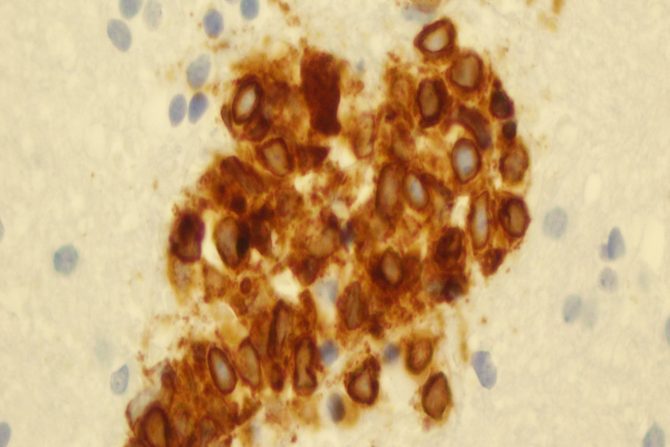

Non Hočkinov limfom može da izazove povećanje i oticanje limfnih čvorova. Uvećani limfni čvorovi na bočnim stranama vrata, u predelu prepona, ispod pazuha, ili iznad ključne kosti mogu se videti i golim okom ili osetiti kao kvržice ispod kože. Obično nisu bolni.

Međutim, iako su uvećani limfni čvorovi čest simptom limfoma, oni su neuporedivo češće uzrokovani infekcijama. Limfni čvorovi koji su manifestacija reakcije organizma na infekciju nazivaju se reaktivni ili hiperplastični limfni čvorovi. Uglavnom su osetljivi na dodir.